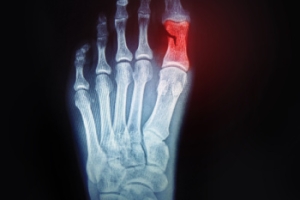

What Toe Fractures Are and How They Happen

A toe fracture is a break in one or more of the small bones in the toes, usually caused by direct trauma, such as stubbing the toe or dropping a heavy object on the foot. These injuries are common and can vary in severity. Symptoms may include sharp pain, swelling, bruising, and difficulty in walking. In some cases, the toe may appear crooked or deformed. Risk factors include weak bone density, participation in contact sports, and walking barefoot in unsafe areas. A podiatrist can provide a thorough evaluation and determine the best treatment to ensure proper healing. If you think you may have fractured your toe, it is suggested that you consult a podiatrist who can accurately diagnose and treat this injury.

Although most people try to avoid foot trauma such as banging, stubbing, or dropping heavy objects on their feet, the unfortunate fact is that it is a common occurrence. Given the fact that toes are positioned in front of the feet, they typically sustain the brunt of such trauma. When trauma occurs to a toe, the result can be a painful break (fracture).

Symptoms of a Broken Toe

- Throbbing pain

- Swelling

- Bruising on the skin and toenail

- The inability to move the toe

- Toe appears crooked or disfigured

- Tingling or numbness in the toe

Generally, it is best to stay off of the injured toe with the affected foot elevated.

Severe toe fractures may be treated with a splint, cast, and in some cases, minor surgery. Due to its position and the pressure it endures with daily activity, future complications can occur if the big toe is not properly treated.

Trauma to the foot, especially the toes, can occur in many ways. Banging them, stubbing them, or dropping something on them are a few different ways this trauma can occur. Given the fact that toes are positioned in front of the feet, they typically sustain the brunt of such trauma. When trauma occurs to a toe, the result can be a painful break or fracture. Another type of trauma that can break a toe is repeated activity that places stress on the toe for prolonged periods of time.

Broken toes can be categorized as either minor or severe fractures. Symptoms of minor toe fractures include throbbing pain, swelling, bruising on the skin and toenail, and the inability to move the toe with ease. Severe toe fractures require medical attention and are indicated when the broken toe appears crooked or disfigured, when there is tingling or numbness in the toe, or when there is an open, bleeding wound present on the toe.

Generally, a minor toe break will heal without long-term complications. However, it is important to discontinue activities that put pressure on the toe. It is best to stay off of the injured toe and immediately get a splint or cast to prevent any more additional movement of the toe bones. You can also immobilize your toe by placing a small cotton ball between the injured toe and the toe beside it. Then, tape the two toes together with medical tape. Swelling can be alleviated by placing an ice pack on the broken toe directly as well as elevating your feet above your head.

Severe toe fractures may be treated with a splint, cast, and in some cases, minor surgery, especially when the big toe has been broken. Due to its position and the pressure the big toe endures with daily activity, future complications can occur if it is not properly treated. Pain associated with minor toe fractures can be managed with over-the-counter pain medications. Prescription pain killers may be necessary for severe toe fractures.

The healing time for a broken toe is approximately four to six weeks. In severe cases where the toe becomes infected or requires surgery, healing time can take up to eight weeks or more. While complications associated with a broken toe are immediately apparent, it is important to note that there are rare cases when additional complications, such as osteoarthritis, can develop over time. You should immediately speak with your podiatrist if you think you have broken your toe due to trauma. They will be able to diagnose the injury and recommend the appropriate treatment options.